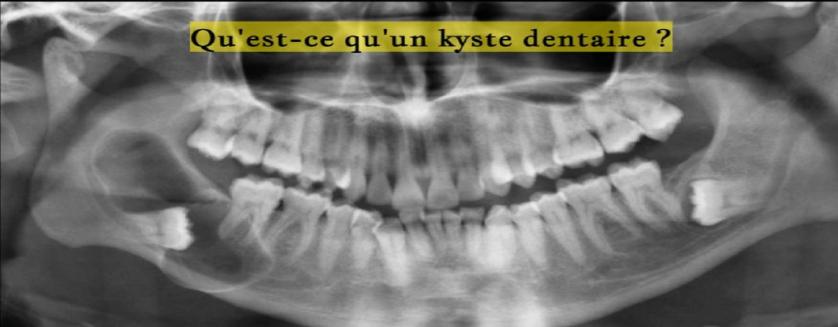

Qu'est-ce qu'un kyste dentaire ?

Le kyste est une tumeur puisqu’elle correspond bien à une augmentation de volume d’un tissu clairement délimitée sans précision de cause.

kyste dentaire, les symptômes, saignements, traitement, inflammation, infection Lire la suite...